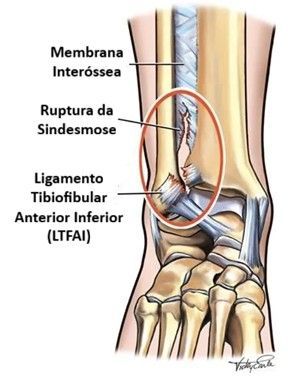

A sindesmose é uma estrutura crucial localizada na parte mais alta do tornozelo, entre os ossos da tíbia (o osso mais longo da canela) e da fíbula (o osso mais fino e lateral da canela). Pense nela como uma "pinça" ou um "arco" que une esses dois ossos, garantindo a estabilidade e a integridade da articulação do tornozelo.

Os principais ligamentos que formam e fortalecem a sindesmose são:

- Ligamento Tibiofibular Anterior Inferior (LTFAI): É o ligamento mais comumente lesionado na entorse da sindesmose. Localiza-se na parte da frente, unindo a tíbia e a fíbula.

- Ligamento Tibiofibular Posterior Inferior (LTFPI): Situado na parte de trás da articulação, é mais forte que o anterior e também contribui para a estabilidade.

- Ligamento Transverso: Uma parte mais profunda do ligamento tibiofibular posterior, que conecta a tíbia e a fíbula, dando suporte adicional.

- Membrana Interóssea: Uma fina, mas resistente, folha de tecido que se estende por toda a distância entre a tíbia e a fíbula, desde o joelho até o tornozelo, ajudando a manter os ossos unidos.

Quando esses ligamentos são esticados ou rompidos, a "pinça" perde sua função, e a estabilidade do tornozelo é comprometida, podendo levar a dor crônica e dificuldade funcional se não tratada adequadamente.